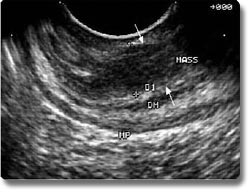

超声内镜检查是近年开发的一种直视性的腔内超声技术,超声探头位于内镜前端,可同时进行电子内镜和超声检查。由于超声探头距病变部位很近,且不受胃肠道气体的影响,能将粘膜下病变及其邻近器官的断层图像清晰地显示。主要用于电子内镜和体外超声等影像技术难以诊断的消化道粘膜下肿瘤的鉴别诊断、胃食管癌的病程分期(肿瘤侵润深度、有无周围淋巴结及邻近器官转移)及胰腺肿瘤、胆总管下端结石等疾病的诊断。在超声内镜的引导下,还可作穿刺活检及介入治疗。